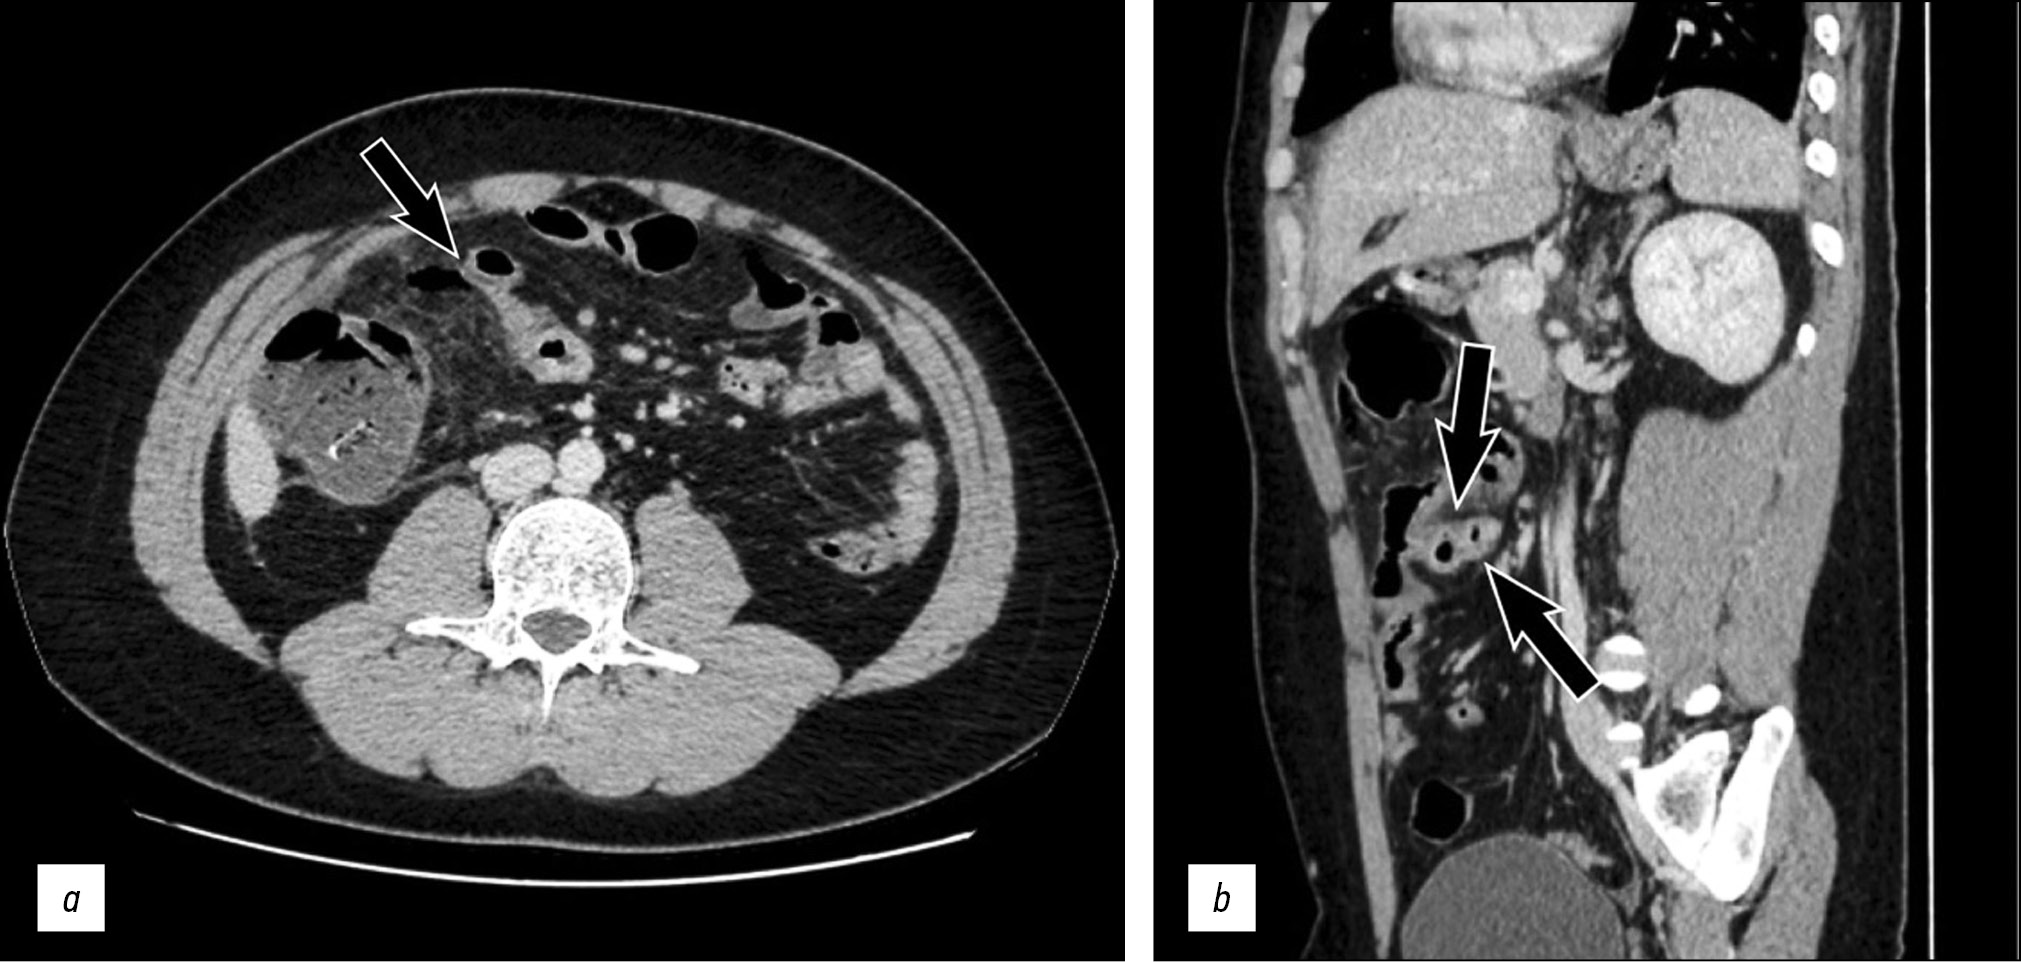

These findings were associated with the presence of certain adjacent gas nuclei with antideclive arrangement, diagnostics for perforation (Fig. 2a, b).

Fig. 2. Axial (a) and sagittal (b) post-contrast computed tomography images showing an intense contrast enhancement of the intestinal wall at the level of the same blind-ended loop (arrows) and some adjacent gaseous nuclei with antideclive arrangement, diagnostic for perforation.